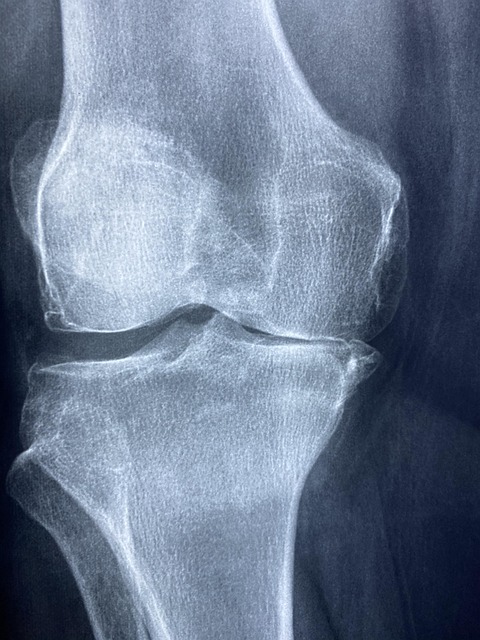

Заболевания суставов — это не только проблема пожилых людей. Современный ритм жизни, недостаток физической активности и неправильное питание приводят к тому, что суставные патологии диагностируются у людей различных возрастов. В данной статье мы разберем основные причины, симптомы и методы лечения заболеваний суставов, а также профилактические меры, которые помогут сохранить их здоровье.

Классификация заболеваний суставов

Заболевания суставов можно разделить на несколько категорий:

| Тип заболевания | Описание |

|---|---|

| Артрит | Воспалительные процессы в суставе, вызванные инфекцией, травмой или аутоиммунными нарушениями. |

| Артроз | Дегенеративные изменения хрящевой ткани, часто связанные с возрастом или физической нагрузкой. |

| Подагра | Накопление мочевой кислоты в суставах, что приводит к их воспалению. |

| Остеопороз | Уменьшение плотности костной ткани, что увеличивает риск переломов и повреждений суставов. |